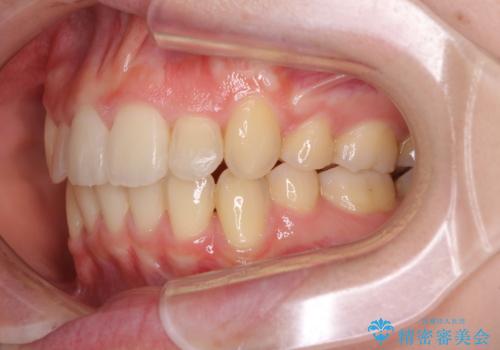

気になる八重歯を治したい ワイヤー装置での抜歯矯正

- 上下の八重歯や乱杭歯を気にして来院され患者様です。

スペースを確保するため、上下左右の第一小臼歯を抜歯し、ワイヤー装置に矯正することとしました。